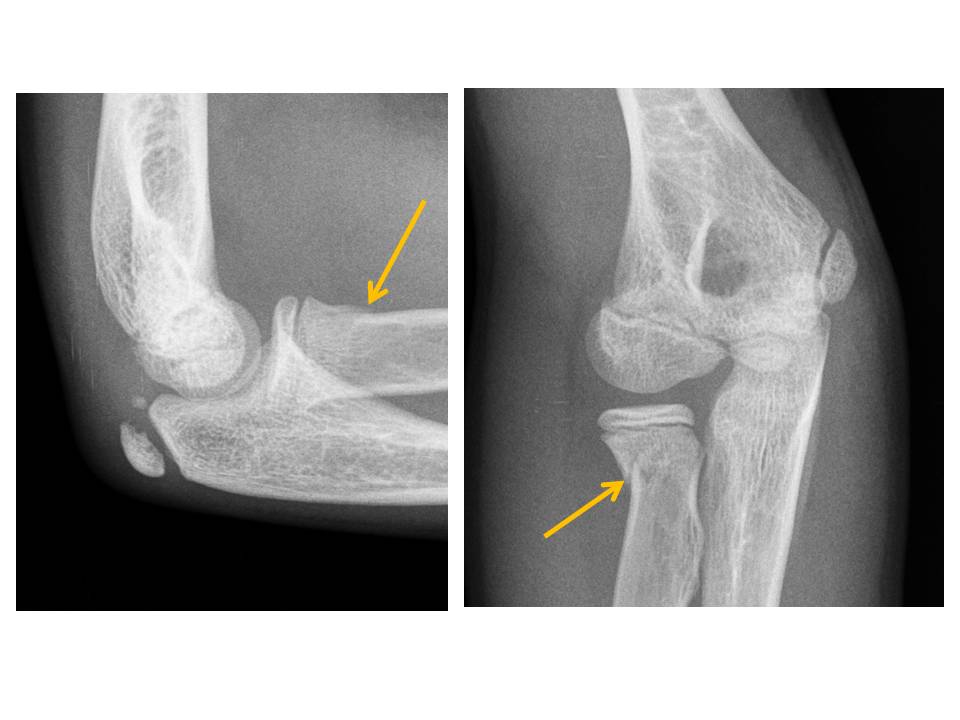

Acute Traumatic Pediatric Elbow Pain

Elbow fracture/malalignment.